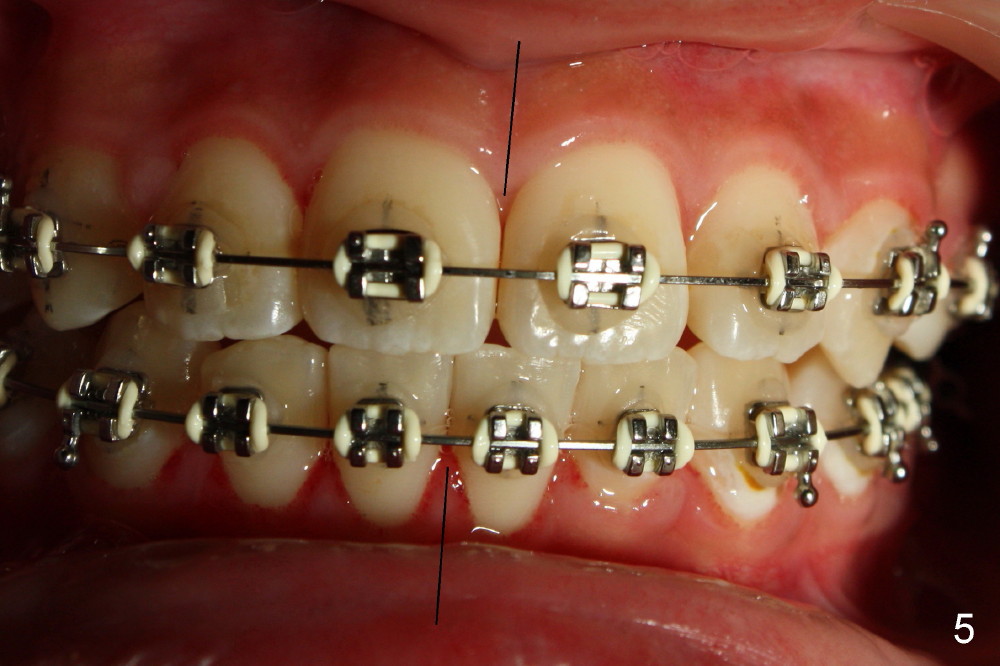

Elastic retraction is instructed to correct dental midline discrepancy (Fig.5).